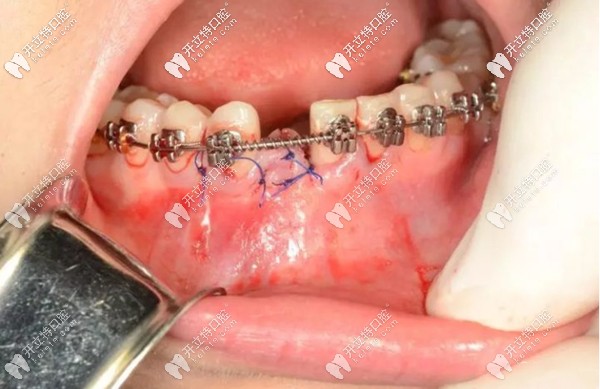

就例如,像我這種情況,下門牙先天缺失一顆,牙槽骨骨量充沛,在正畸進(jìn)行到一半,也就是可以容納一顆種植體的時(shí)候,由種植醫(yī)生為我做了微創(chuàng)種植手術(shù)。

正畸過(guò)程中做種植牙的示意圖

看到?jīng)],缺牙部位已經(jīng)埋入了一顆種植體,而正畸的托槽和弓絲裝置還在牙齒上發(fā)揮這自己的作用。

然后,將種植手術(shù)部位進(jìn)行縫合,靜待植體和牙槽骨的結(jié)合,預(yù)計(jì)3個(gè)月左右的時(shí)間。之后安裝基臺(tái)、牙冠,這顆種植牙大概需要半年左右的時(shí)間才能“大功告成”。